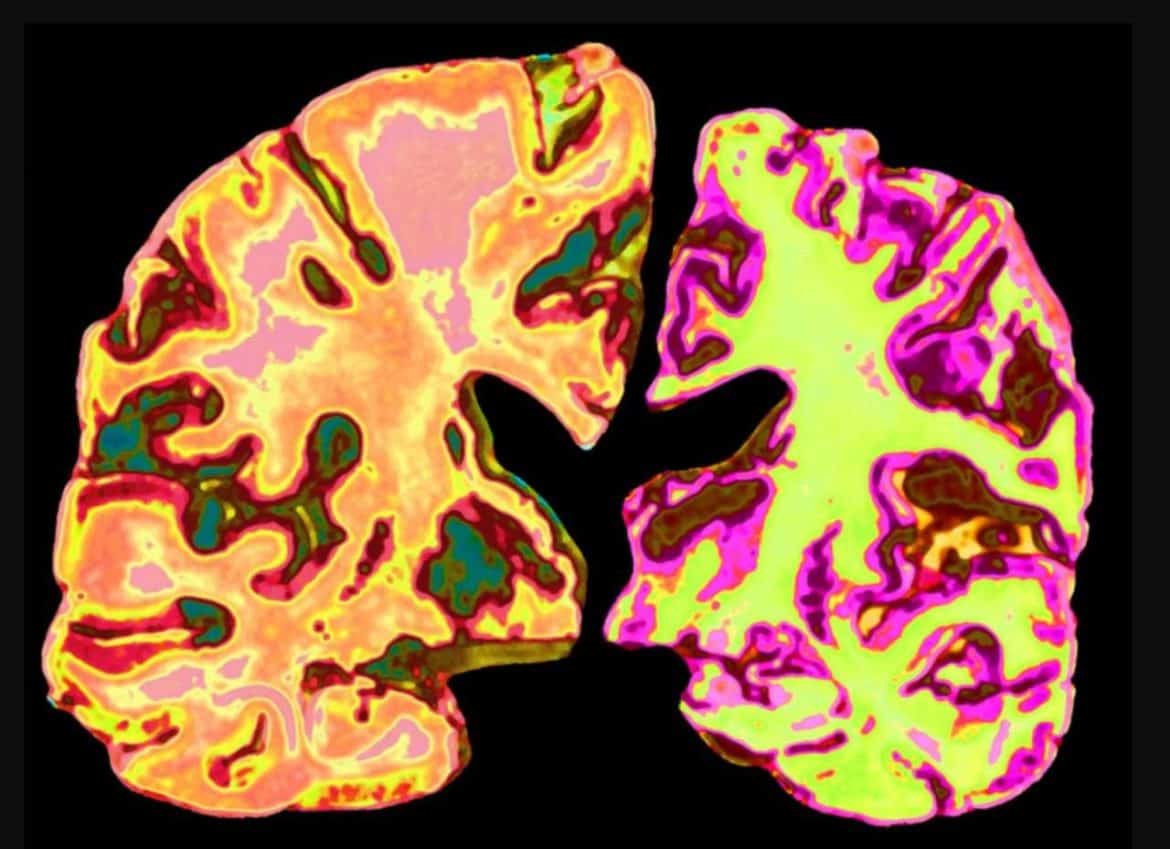

اختراق علمي: انخفاض الليثيوم قد يكون مفتاحًا لفهم وعلاج الزهايمر

كشفت دراسة امتدت على مدار سبع سنوات، ونُشرت نتائجها في مجلة Nature العلمية، عن أن انخفاض مستوى الليثيوم في الدماغ قد يكون عاملًا محتملًا في تطور مرض الزهايمر.

وأوضحت النتائج أن الليثيوم يلعب دورًا أساسيًا في الدماغ السليم، حيث يحافظ على الروابط بين الخلايا العصبية، ويساهم في تكوين الغلاف الواقي للألياف العصبية (الميالين)، إضافة إلى مساعدته لخلايا متخصصة على تنظيف الدماغ من الفضلات البروتينية الضارة.

هذا الاكتشاف يفتح آفاقًا جديدة أمام الباحثين لتطوير طرق مبتكرة لتشخيص المرض في مراحله المبكرة، فضلًا عن ابتكار استراتيجيات علاجية قد تُحسن بشكل كبير من نوعية حياة ملايين المصابين بالزهايمر حول العالم.